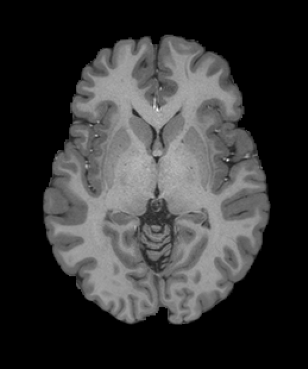

Inverse consistent rigid, affine, nonparametric, and MLP registration. We train networks on MNIST 5s using the methods in Secs. 3 and 4, demonstrating that the resulting networks are inverse-consistent. Our TwoStepConsistent (TSC) operator can be used on any combination of the networks defined in Sec. 3. For demonstrations, we join an MLP registration network to a vector field registration network, and join two affine networks to two vector field networks. Fig. 2 shows successful inverse-consistent sample registrations.

| Moving Image | Warped Image | Fixed Image | Moving Image | Warped Image | Fixed Image |